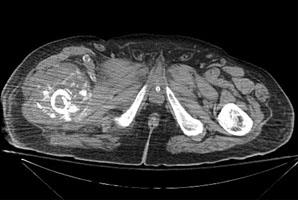

- Click on the image for a larger versionBAxial CT. This image through the fracture demonstrates a large soft tissue mass with extensive bony destruction.